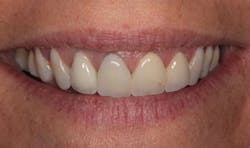

In Figure 1, you can see a close-up view of her smile as it was when she presented. She recently had noticed a fracture in both central incisor crowns and, since replacement was necessary, wanted to investigate the possibilities for improvement. The retracted facial view can be seen in Figure 2. Clinical and radiographic examination showed me that her overall dental health was good, with no periodontal disease or active caries. The patient expressed an interest in widening her smile and achieving a lighter color. The shade she desired was OM1 on the Vita Toothguide 3D-Master shade guide (figure 3).

Figure 1: Close-up view of the patient’s smile before treatment